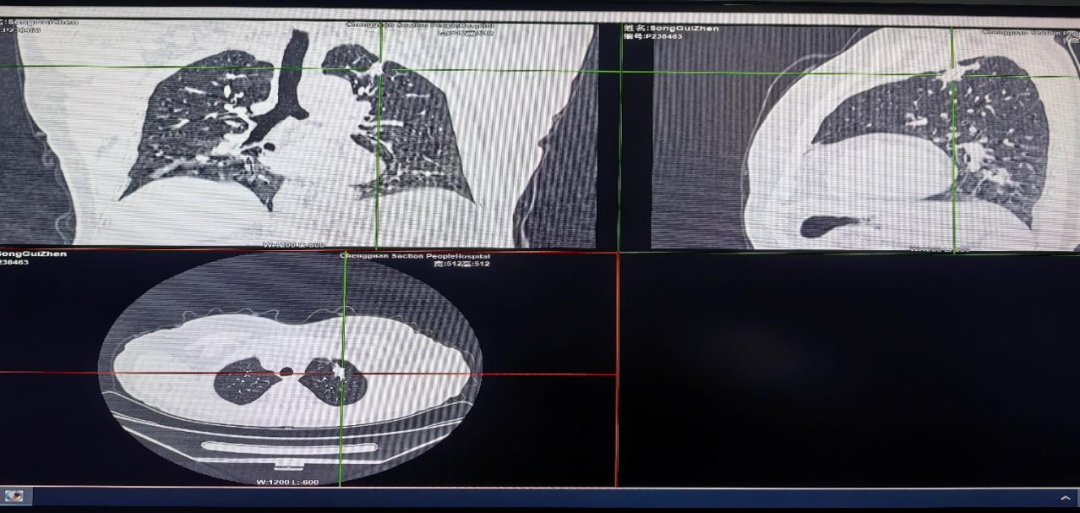

患者为 76 岁女性,因咳嗽、咳痰前来就诊,通过高分辨薄层CT确定其左固有上叶病变位于LB1+2a1βy,通过测距法明确病灶距离左固有上叶开口约 5.2~5.8cm。

病变胸部影像